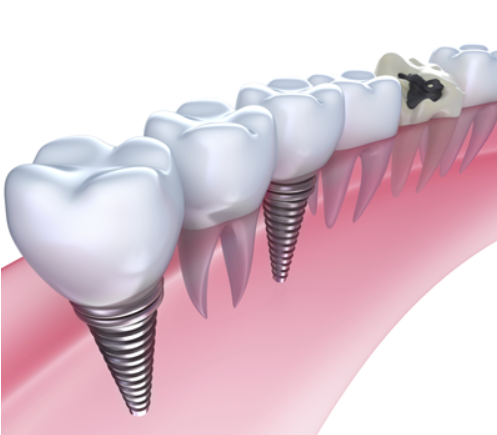

임플란트 재수술이란 기존의 임플란트가 다양한 원인으로 이상 증상을 보이는 경우 이미 식립되어 있는 임플란트 제거 수술을 진행하고 새로운 임플란트 재식립을 하는 수술이입니다.

임플란트 자체는 반영구적인 성질을 가지고 영구적으로 기능해야 하지만, 간혹 수술 시 발생한 문제나 개인의 부주의로 인해 임플란트에 손상이 발생해 재수술을 받아야 하는 경우도 있는데요.

간략히 말씀드리면 임플란트를 식립한 자리에서 통증이 느껴지거나 주위 잇몸뼈가 녹아 내리거나 기존 임플란트로 인한 치열의 변형 또는 망가진 경우, 임플란트가 빠지거나 부서지는 등의 증상이 나타나면 재수술이 필요합니다.